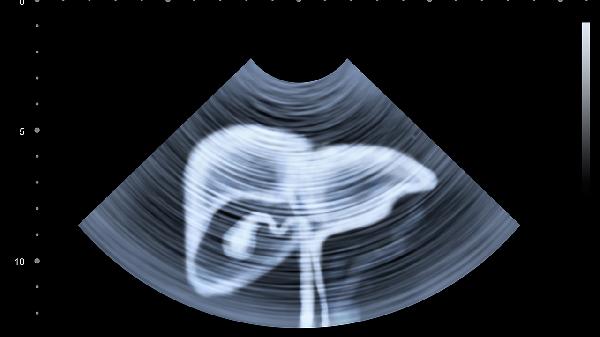

肝占位性病變是一種影像學上的描述,主要是肝臟影像學中的異常信號區(qū)域。肝占位性病變可能是良性病變或惡性腫瘤;可能是原發(fā)性病變,也可能是轉移性病變。常見的良性疾病包括肝囊腫、肝血管瘤、肝腺瘤、肝局灶性結節(jié)樣增生。惡性腫瘤主要是肝癌,可分為原發(fā)性肝癌和轉移性癌。原發(fā)性肝癌包括肝細胞型肝癌、膽管細胞型肝癌和兩者的混合型。轉移性肝癌主要是由肝轉移引起的其他病變,更常見的是結直腸腫瘤。肝占位需要通過加強CT或磁共振和腫瘤標志物來進一步判斷良惡性,必要時還可以在影像學的指導下進行穿刺活檢。